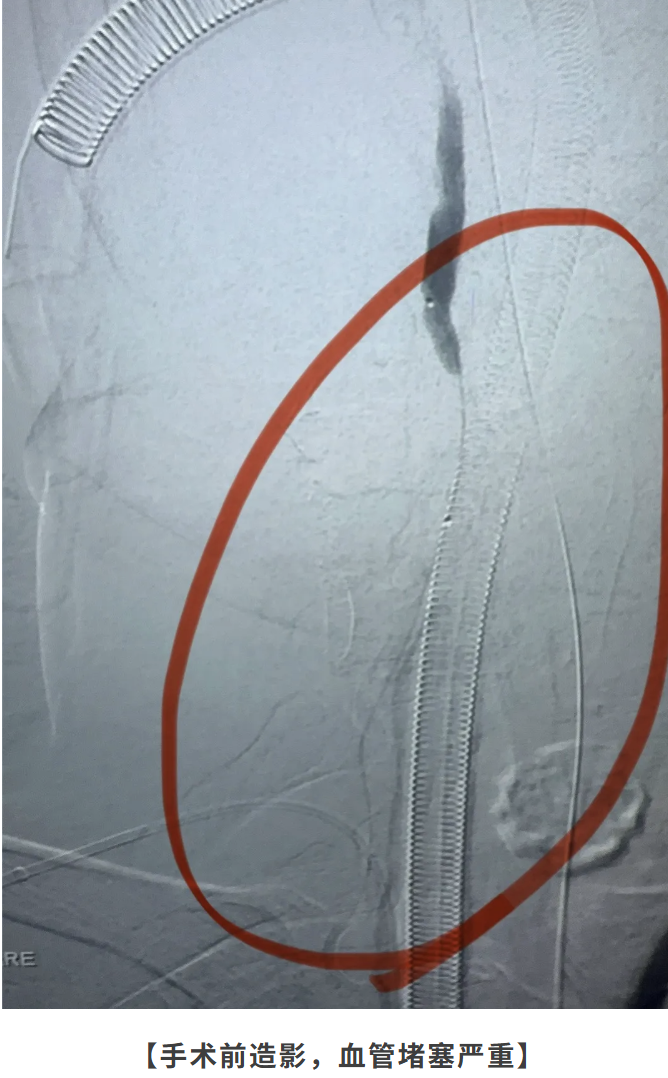

手术团队与麻醉科进行了缜密的术前准备。术中,贾颐主任发现情况比预想的还要复杂——患者基底动脉开口处就完全堵死,整个颅内大血管完全不显影。贾颐主任凭借丰富的经验和稳准的手法,通过手臂桡动脉入路,运用导管和支架技术,成功“探入”闭塞的血管深处。

惊心动魄 取出15公分长血栓

经过一番精细操作,贾颐主任成功取出了一条长约15公分的血栓,彻底疏通了这条“生命主干道”。术后造影显示,原本消失的基底动脉及其分支血管完美显影,血流恢复通畅!